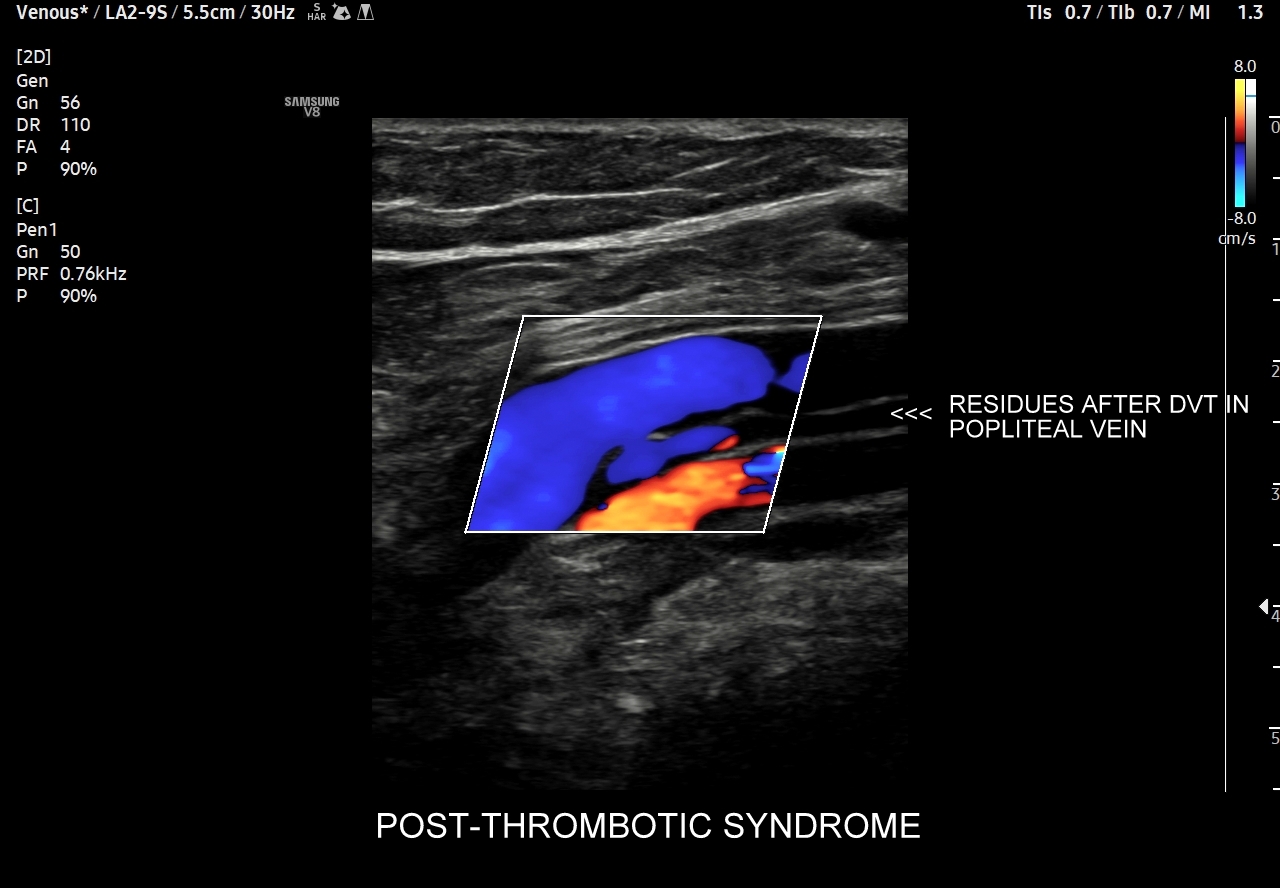

42. Patologie żył kończyn dolnych, w tym niewydolność żył powierzchownych i głębokich, żylaki, zakrzepica żył powierzchownych, zakrzepica żył głębokich, zespół pozakrzepowy.

Dzień żylny w ramach Kursu dedykowany jest dopplerowskiemu badaniu żył, w szczególności w obrębie kończyn dolnych. Otóż to właśnie w tym obszarze ujawniają się najczęściej choroby układu żylnego takie jak zakrzepica żył głębokich, zakrzepica żył powierzchownych, niewydolność żył powierzchownych i żylaki podudzi, niewydolność żył głębokich i zespół pozakrzepowy, które to badający lekarz powinien umieć rozpoznać. W trakcie interdyscyplinarnego Kurs USG Doppler Cedum ® omawiane są również hemodynamika krążenia żylnego w fizjologii i w stanach patologicznych; cele diagnostyczne, w tym planowanie zabiegów angiochirurgicznych i endowaskularnych w obrębie żył; a także nauczane są techniki funkcjonalnego badania żył kończyn dolnych i żył miednicy. Kurs obejmuje także tematykę dotycząca żyły głównej dolnej i jej brzusznych dopływów, żył szyjnych oraz żył kończyn górnych.